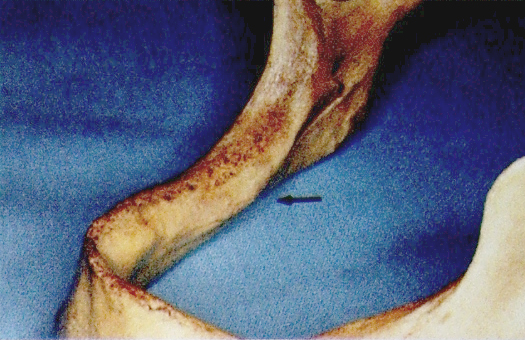

8.下颌舌骨嵴(mylohyoid ridges)

位于下颌骨后部的舌面,从第三磨牙斜向前磨牙区,由宽变窄。

是下颌舌骨肌在下颌骨的附着处,肌纤维向前向下止于舌骨,起降下颌和拉舌骨向前的作用。即使最大程度收缩时,也允许义齿边缘延长超过下颌舌骨嵴。

表面覆盖粘膜较薄,下方有不同程度的倒凹,基托组织面应缓冲。